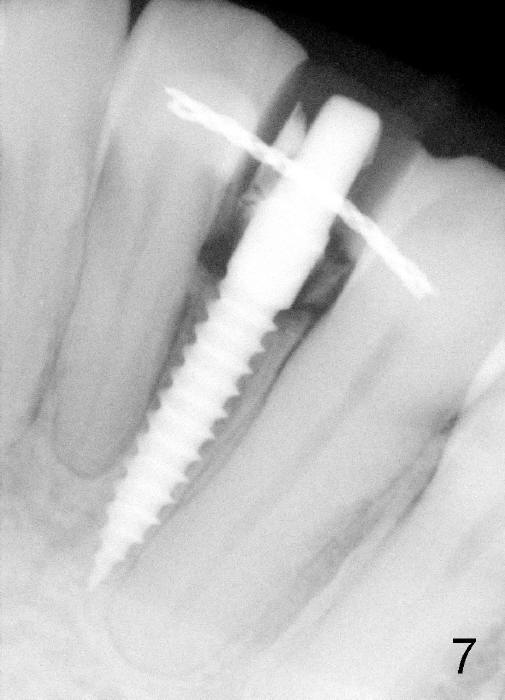

Within the first several days postop, the patient reports mild tenderness from one of the neighboring teeth. Otherwise she is doing fine. Again due to finance, she does not return for restoration for more than 1 year. PA taken 10 months postop shows that there is no abnormality (Fig.7). In fact bone resorption occurs gradually over 2 years 2 months postop, manifested as the 1st thread supracrestal (Fig.8 <). When the 1-piece implant is reprepped for impression 2 years 2 months postop, the micro threads are found apical to the prep margin (Fig.9). The nervous patient has had occasional tooth sensitivity 5 years postop. A narrower implant is more suitable for this case (2.0 or 2.5 mm).